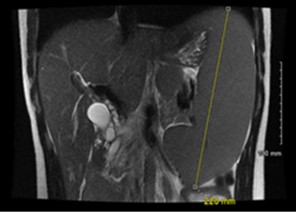

Right upper quadrant ultrasound revealed a distended gallbladder with cholelithiasis and no evidence of cholecystitis. Magnetic resonance cholangiopancreatography (MRCP) demonstrated biliary ductal dilation to 0.9 cm (reference range, 0.18 to 0.6 cm) (Figure 1), edematous pancreatitis, and splenomegaly to 22 cm (reference range, 12 to 14 cm) (Figure 2). Endoscopic retrograde cholangiopancreatography (ERCP) was notable for removal of a 5-mm pigmented stone, and laparoscopic cholecystectomy was performed without complications. Concurrent splenectomy with laparoscopic cholecystectomy was a consideration for this patient. However, given the patient's stable hemoglobin levels and recommendations that patients receive pneumonia, meningitis, and flu vaccinations at least two weeks prior to splenectomy, the procedure was deferred to be scheduled electively at outpatient follow-up.